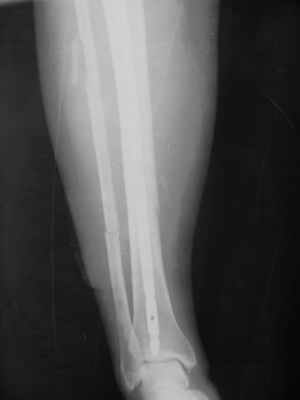

Здравствуйте уважаемые коллеги. Позвольте поделиться опытом применения интрамедуллярного остеосинтеза большеберцовой кости имплантатами компании ?Остеомед" с запатентованной прицельно-навигационной системой для дистального блокирования ?Интерлок". Для определения длинны и диаметра стержня использовали линейку-шаблон, позволяющей с легкостью рассчитать длину и диаметр стержня с проекцинно искаженными размерами, как конечности, так и линейки-шаблона.Дистракцию производили с помощью спицевого дистрактора с последующей закрытой репозицией отломков винтами Шанца. Все основные этапы производили по методике АО, гарантированное дистальное блокирование достигается за счет центрирования отверстий, путем контролирования смещения стержня в костномозговом канале в сагиттальной плоскости. Клинический пример:Больная Я. 45 лет, пострадала в результате случайного падения на улице 19.12.2005., имеет место открытый 1 степени перелом обеих костей левой голени со смещением отломков.произведена закрытая репозиция перелома с последующим введением стержня (на данном этапе производился рентген-контроль)Убедившись в достаточной репозиции перелома, произведено дистальное и проксимальное блокирование интрамедуллярного стержня.Общее время затраченное на оперативное вмешательство составило 45 минут.